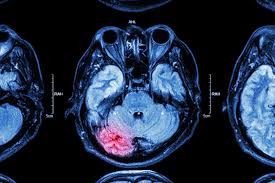

MRI imaging is very useful for seeing the brain and nerves. It can detect:

• Spot and monitor the growth of brain tumours